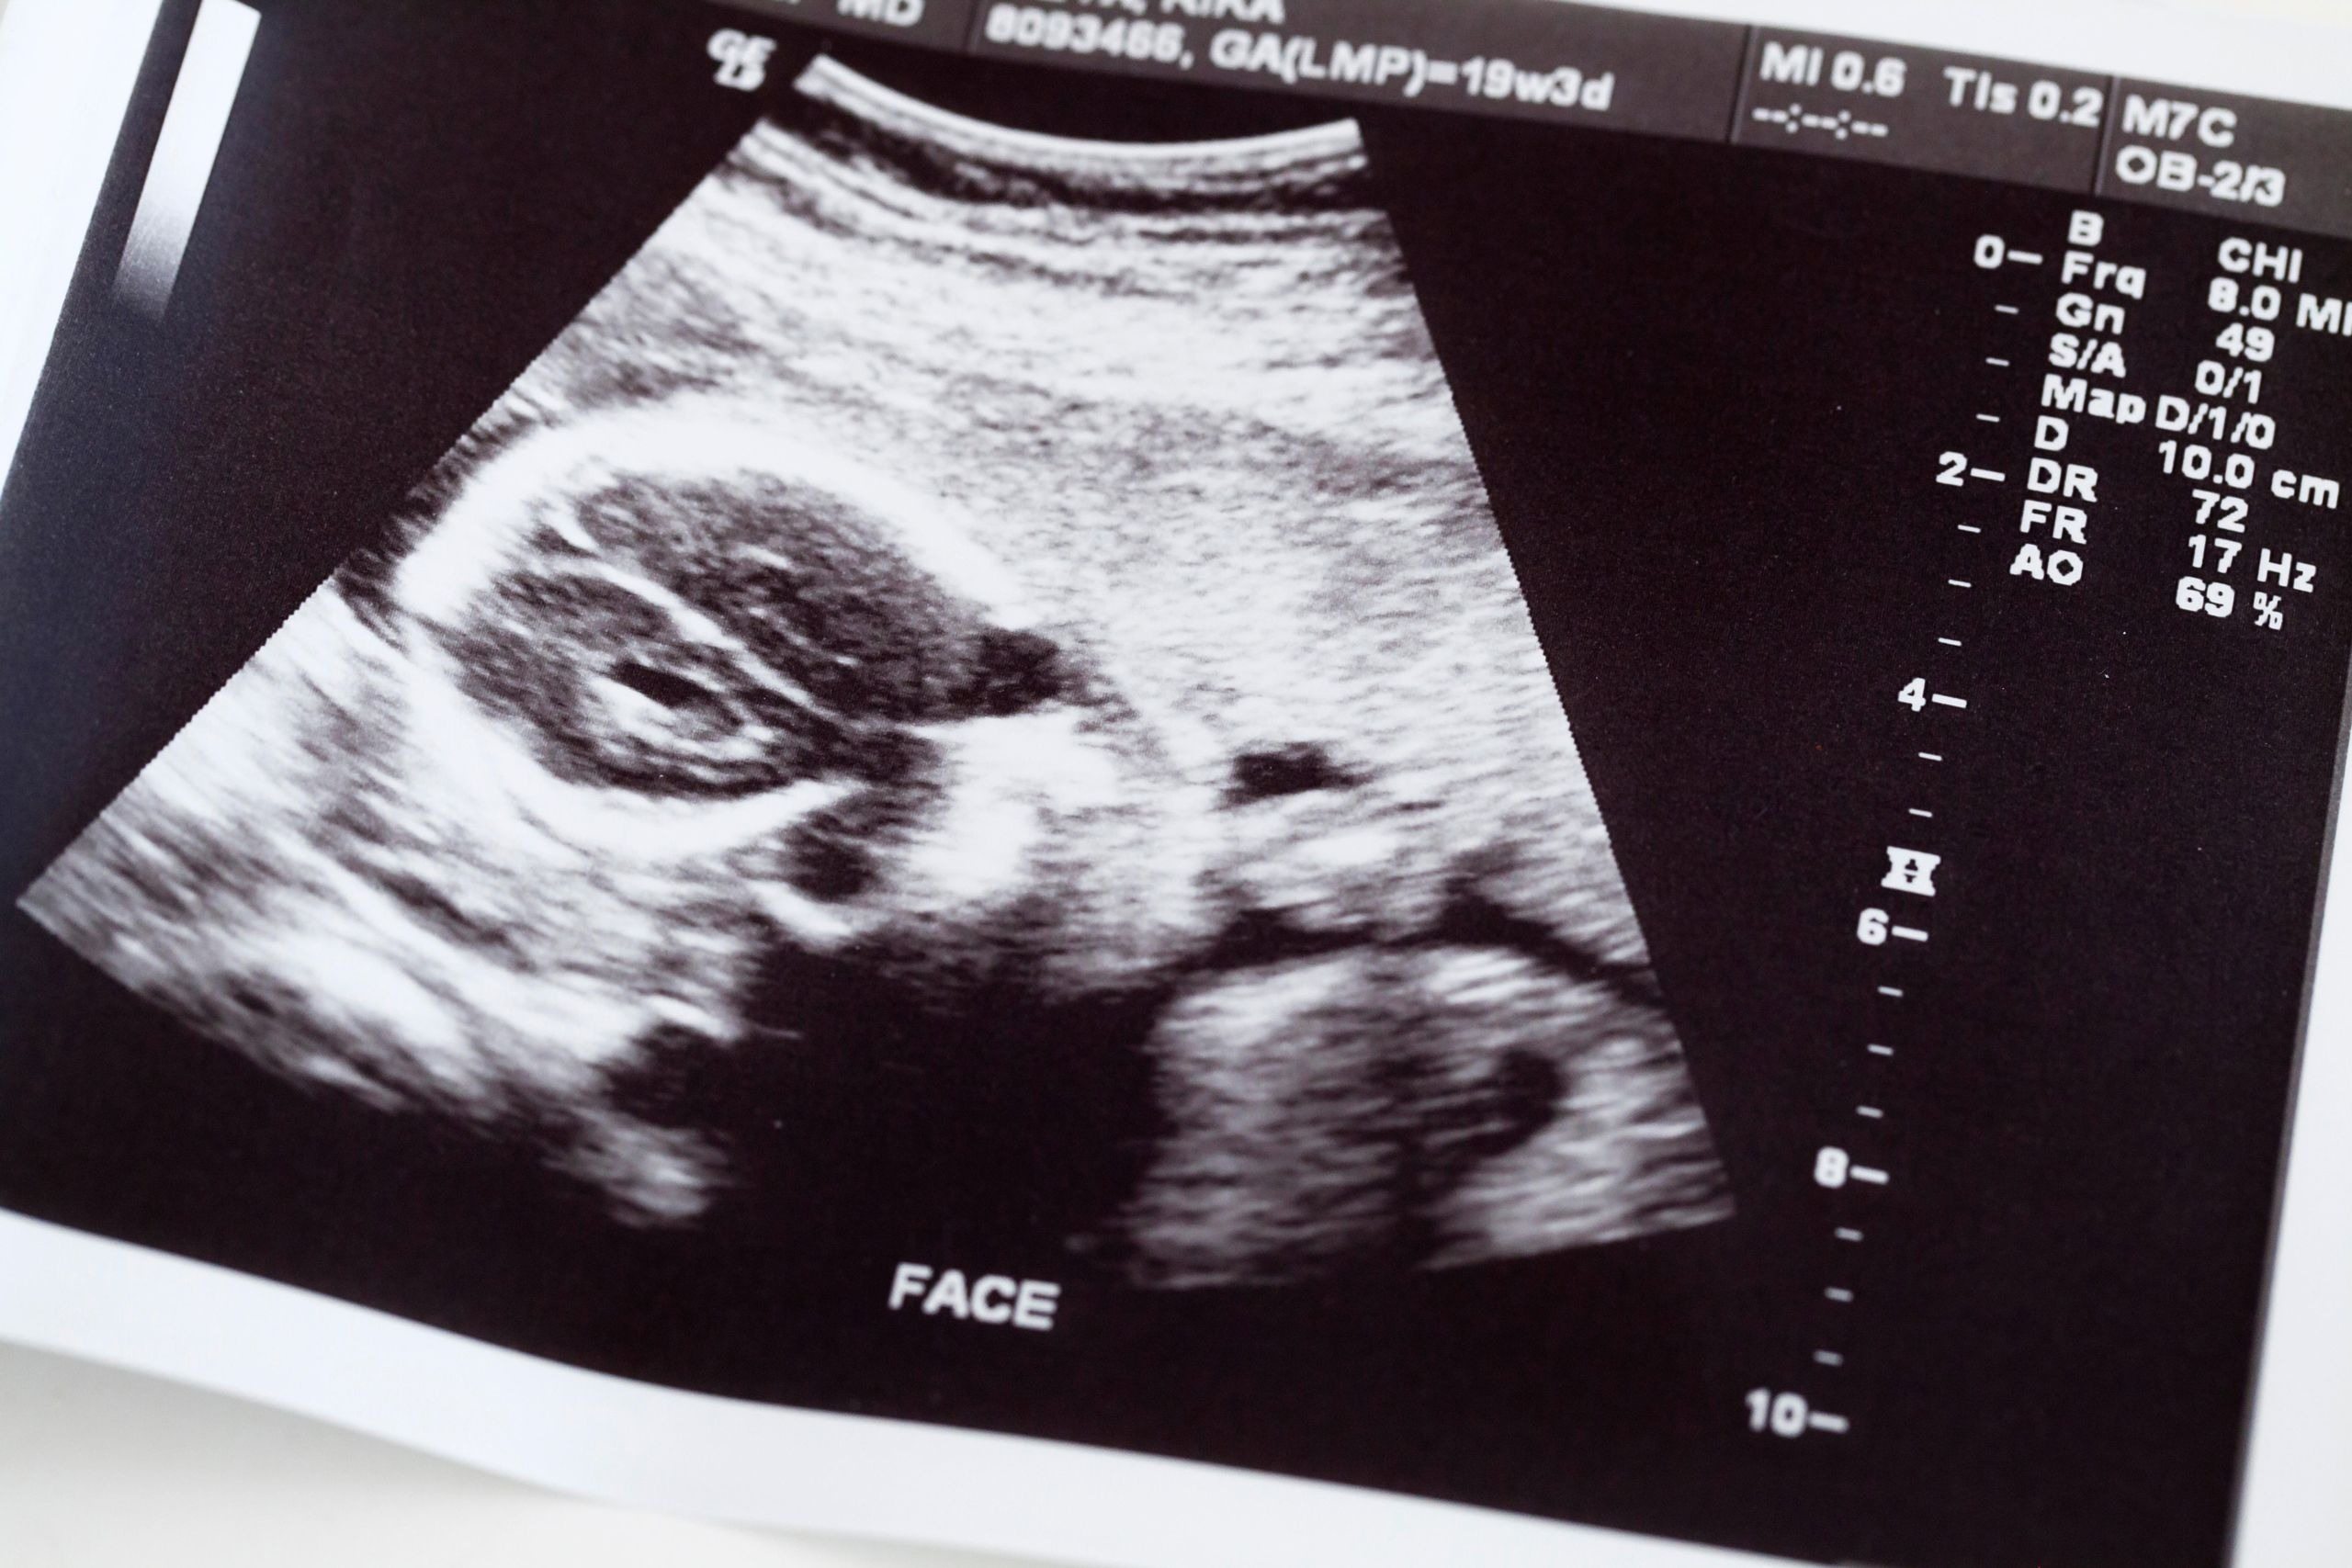

Lily tinha certeza de que o pior já havia passado.

Após um longo e exaustivo trabalho de parto, dois bebês nasceram: um menino, Ezequiel, e uma menina, Zahra.